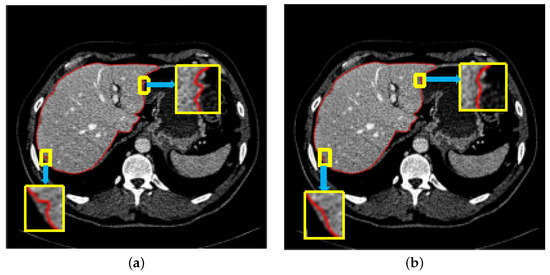

We take the result after region growth as the initial picture of RD level set to segment, and then refine and track the segmented liver part by using its leak resistance and noise resistance. The experimental results are shown in Figure 5. It is obvious that RD level set can refine and segment the liver well and deal with the leakage of the liver boundary.

Figure 5.

Comparison before and after using RD level set: (a) Segmentation effect before using RD level set. (b) Segmentation effect after using RD level set.